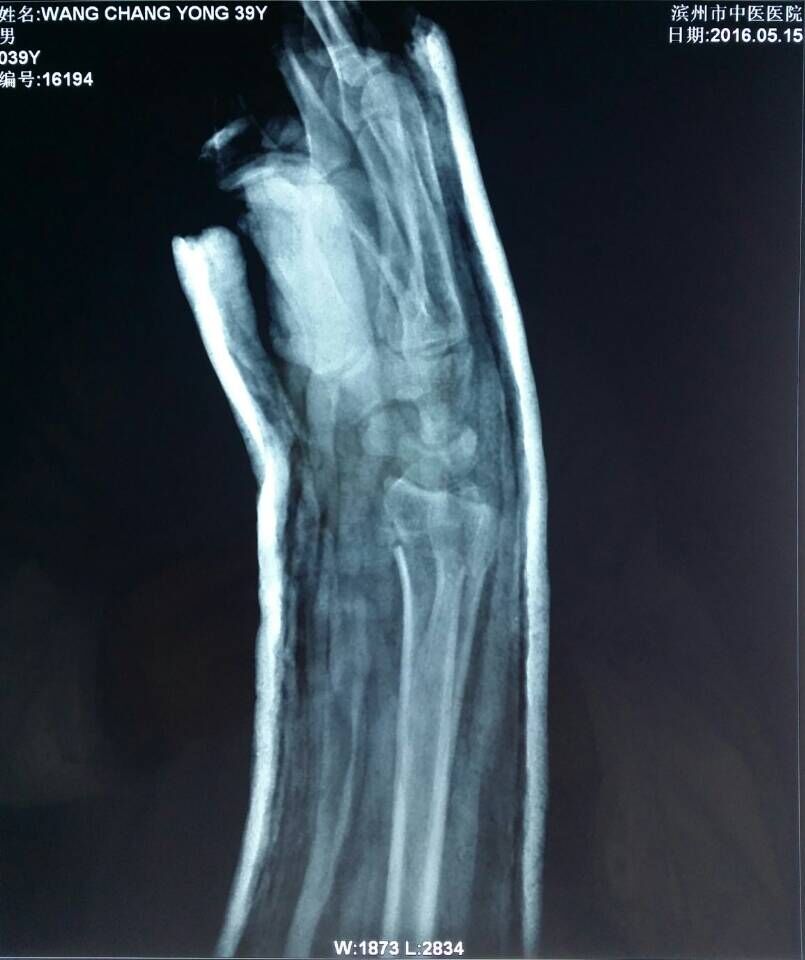

患者王某,男,39岁,踢足球时摔伤右腕关节,右腕部肿胀疼痛、活动受限2小时来我院骨伤科就诊。骨伤科刘陆勇大夫及时安排患者进行X片拍照,X-ray片(图1,2)示:右桡骨远端骨折,远端向桡侧、背侧移位,近端向掌侧移位,右端尺骨茎突骨皮质不连续,见游离骨片影,初步诊断为“桡骨远端骨折”。在确定骨折损伤程度后,刘陆勇大夫和杨晓晓大夫采用中医传统整复手法,给予患者行手法整复石膏外固定,整复后患者再次行x-ray检查(图3,4),x线片显示复位情况良好,效果显著。此次治疗使患者避免切开手术及二次手术取内固定的痛苦,最大限度地减轻了病人的经济负担,受到了病人的一致好评。